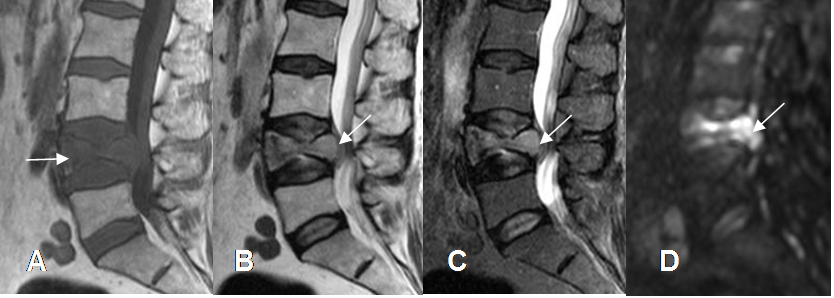

Fig 32. Enfermedad metastásica.

A: RM sagital en T1. Lesión hipointensa en el cuerpo de L4.

B: RM sagital en T2 y C: RM sagital en STIR. Pérdida de altura e hiperintensidad en L4, con

borde posterior convexo que comprime el saco dural.

D: RM difusión en sagital. Lesión hiperintensa, que sugiere origen tumoral.